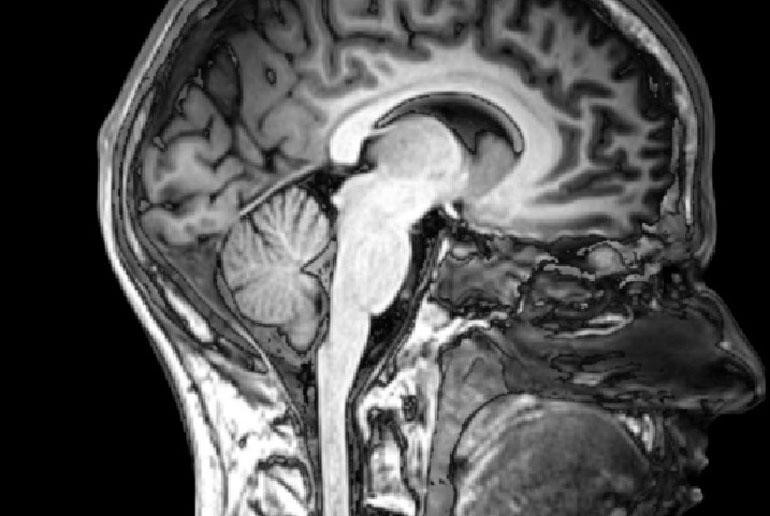

ปรับปรุงคุณภาพของข้อมูลภาพสมองใน MRI –

Brain Imaging หรือ Neuroimaging ดำเนินการเพื่อประเมินความผิดปกติของสมองและรับประกันการทำงานที่เหมาะสม การถ่ายภาพสมองช่วยวินิจฉัยโรคทางสมองและปรับปรุงการวิจัยเกี่ยวกับสมองของมนุษย์ แม้ว่าสิ่งเหล่านี้จะเป็นเพียงข้อดีบางประการของการถ่ายภาพสมอง แต่ MRI (Magnetic Resonance Imaging) ต้องเผชิญกับปัญหาใหญ่ในระหว่างกระบวนการ คุณภาพของข้อมูลที่ลดลงเกิดขึ้น เนื่องจากผู้ป่วยขยับศีรษะระหว่างการสแกน MRI จึงเป็นอุปสรรคต่อการวิเคราะห์สมองและผลการวินิจฉัยที่ผิดพลาด ด้วยความช่วยเหลือและซอฟต์แวร์ ML เช่น FIRMM ที่ช่วยตรวจสอบข้อมูลที่เกี่ยวข้องกับสมองแบบเรียลไทม์และให้ตัวชี้วัดเกี่ยวกับคุณภาพของข้อมูล พัฒนาภายใต้ Linux OS และใช้งานได้เฉพาะในแพลตฟอร์ม Ubuntu และ CentOS เท่านั้น